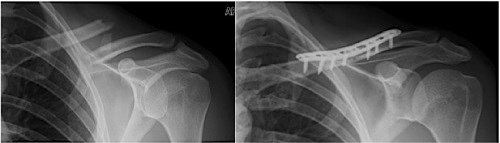

The current question, however, is whether the success of operative management should also be applied to all or some of the fractures that could heal perfectly well on their own. Unlike the robust data that helps us understand who should take an aspirin a day, or whether or not ongoing rider training has utility, there is not a lot of data to help decide about plating your clavicle fracture. The technique has been around for more than 20 years, but trials comparing operation versus sling have few patients and are generally limited to middle third fractures. A recent trial (ages: 5 to 21) examined less than 100 patients in total and concluded that both approaches were equivalent. Similar findings have been noted in adults in several comparisons. While new drug trials need only prove that the new drug isn’t worse than the one already in use, trials of operative techniques should demonstrate a benefit, since the operation generally includes additional risks you don't have without operation. Complications have been well described after operation, many of which, in retrospect, are believed to be avoidable.

Remember that every operation also “buys” you the risks of anesthesia, infection at the site of operation, injury to surrounding structures, and the potential for another operation, especially in the event of infection. Hardware (the metal plates and the screws, and sometimes wires) can also become infected, loosen, and may need to be removed. Operations like a plate and screws may be simple for your surgeon, but carry important and measurable risk that should be balanced against the benefits of the procedure. This is an important part of your discussion and is similar to evaluating the benefits of the upgraded options for your new bike against the downsides of the sucking sound made by money leaving your wallet.